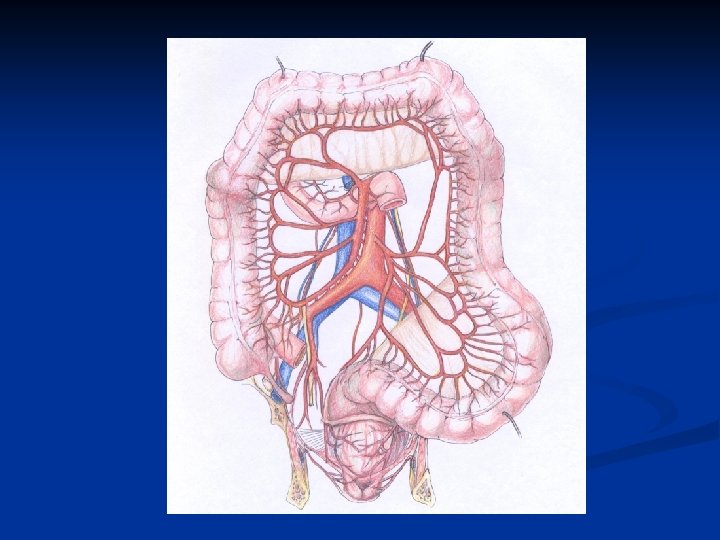

Diverticulosis of the Colon I. Diverticula of the colon are acquired herniations of colonic mucosa protruding through the circular muscle and the wall of large bowel. Localisation - usually in the left part of the large bowel ( sigmoid colon is involved in 90% cases), but they can occur everywhere in large bowel Ethiology - muscular incoordination and hypertrophy resulting in increasing segmentation and intraluminal pressure.